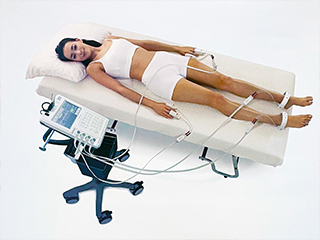

インボディ

体を構成する基本成分である体水分・タンパク質・ミネラル・体脂肪を定量的に分析し、栄養状態に問題がないか、体がむくんでいないか、身体はバランスよく発達しているかなど、人体成分の過不足を評価する検査です。